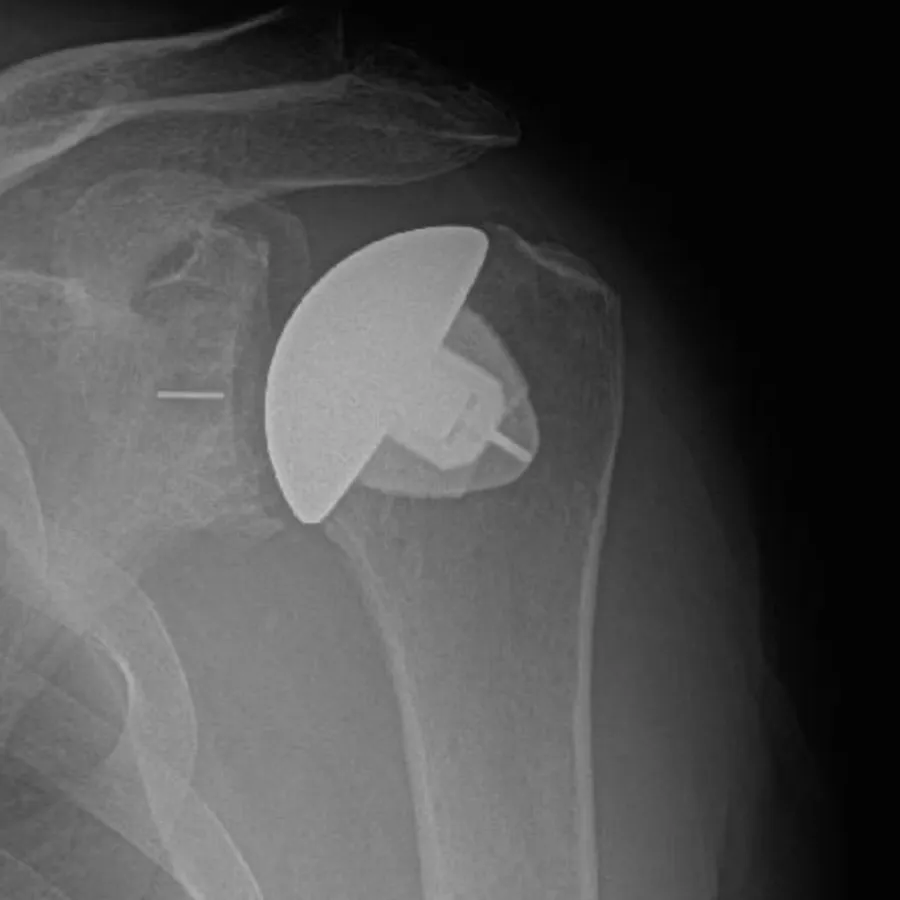

X-ray of shoulder showing a partial shoulder joint replacement implant inside the bone.

Partial Shoulder Replacement (Hemiarthroplasty):

In this procedure, only the ball of the joint is replaced with a prosthetic. It is generally recommended for patients with damage to the humeral head but a relatively healthy socket. Additionally, it is indicated for younger patients with high activity levels that put them at risk for loosening of the socket component. Hemiarthroplasty can also be utilized in cases of severe fractures.